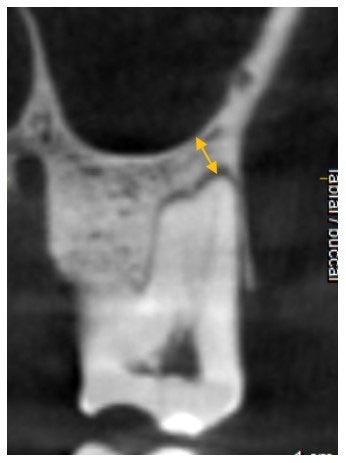

To allow impartial measurements at each of the three levels of data collection, reference lines were placed, as shown in Figure 2. To do this, the most mesial points of the mesiobuccal and palatal roots of the tooth were determined and connected by a straight line, and its halfway point was denoted as point mid-mesial (MM). Similarly, a straight line connecting the most distal points of the mesiodistal and palatal roots was used to establish a point called mid-distal (MD), and another connecting the most buccal aspects of the two buccal roots was used to establish the point designated mid-buccal (MB). After that, the distance between points MM and MD was recorded as the mesiodistal width of the IRS (MDW). Similarly, the buccopalatal IRS width (BPW) was recorded as the measurement from MB to the most buccal point of the palatal root.

Figure 2.

Buccopalatal width (BPW) and mesiodistal width (MDW) measurements were recorded at each of the crestal, middle, and apical levels of each molar IRS.